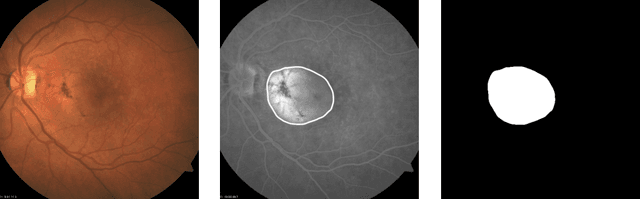

This work aims to research an automatic method for detecting Age-related Macular Degeneration (AMD) lesions in RGB eye fundus images. For this, we align invasively obtained eye fundus contrast images (the "golden standard" diagnostic) to the RGB ones and use them to hand-annotate the lesions. This is done using our custom-made tool. Using the data, we train and test five different convolutional neural networks: a custom one to classify healthy and AMD-affected eye fundi, and four well-known networks: ResNet50, ResNet101, MobileNetV3, and UNet to segment (localize) the AMD lesions in the affected eye fundus images. We achieve 93.55% accuracy or 69.71% Dice index as the preliminary best results in segmentation with MobileNetV3.